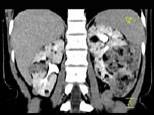

问题 女,36岁,左侧腰痛2 年余,CT检查如图所示,下列说法错误的是 ( )

选项 A、考虑为肾癌 B、考虑为双肾错构瘤 C、左肾病灶中可见脂肪密度灶,该区增强时也无强化 D、右肾中极可见一小的类圆形混杂密度病灶 E、左肾下极可见一混杂密度病灶,其边界尚清

答案 A